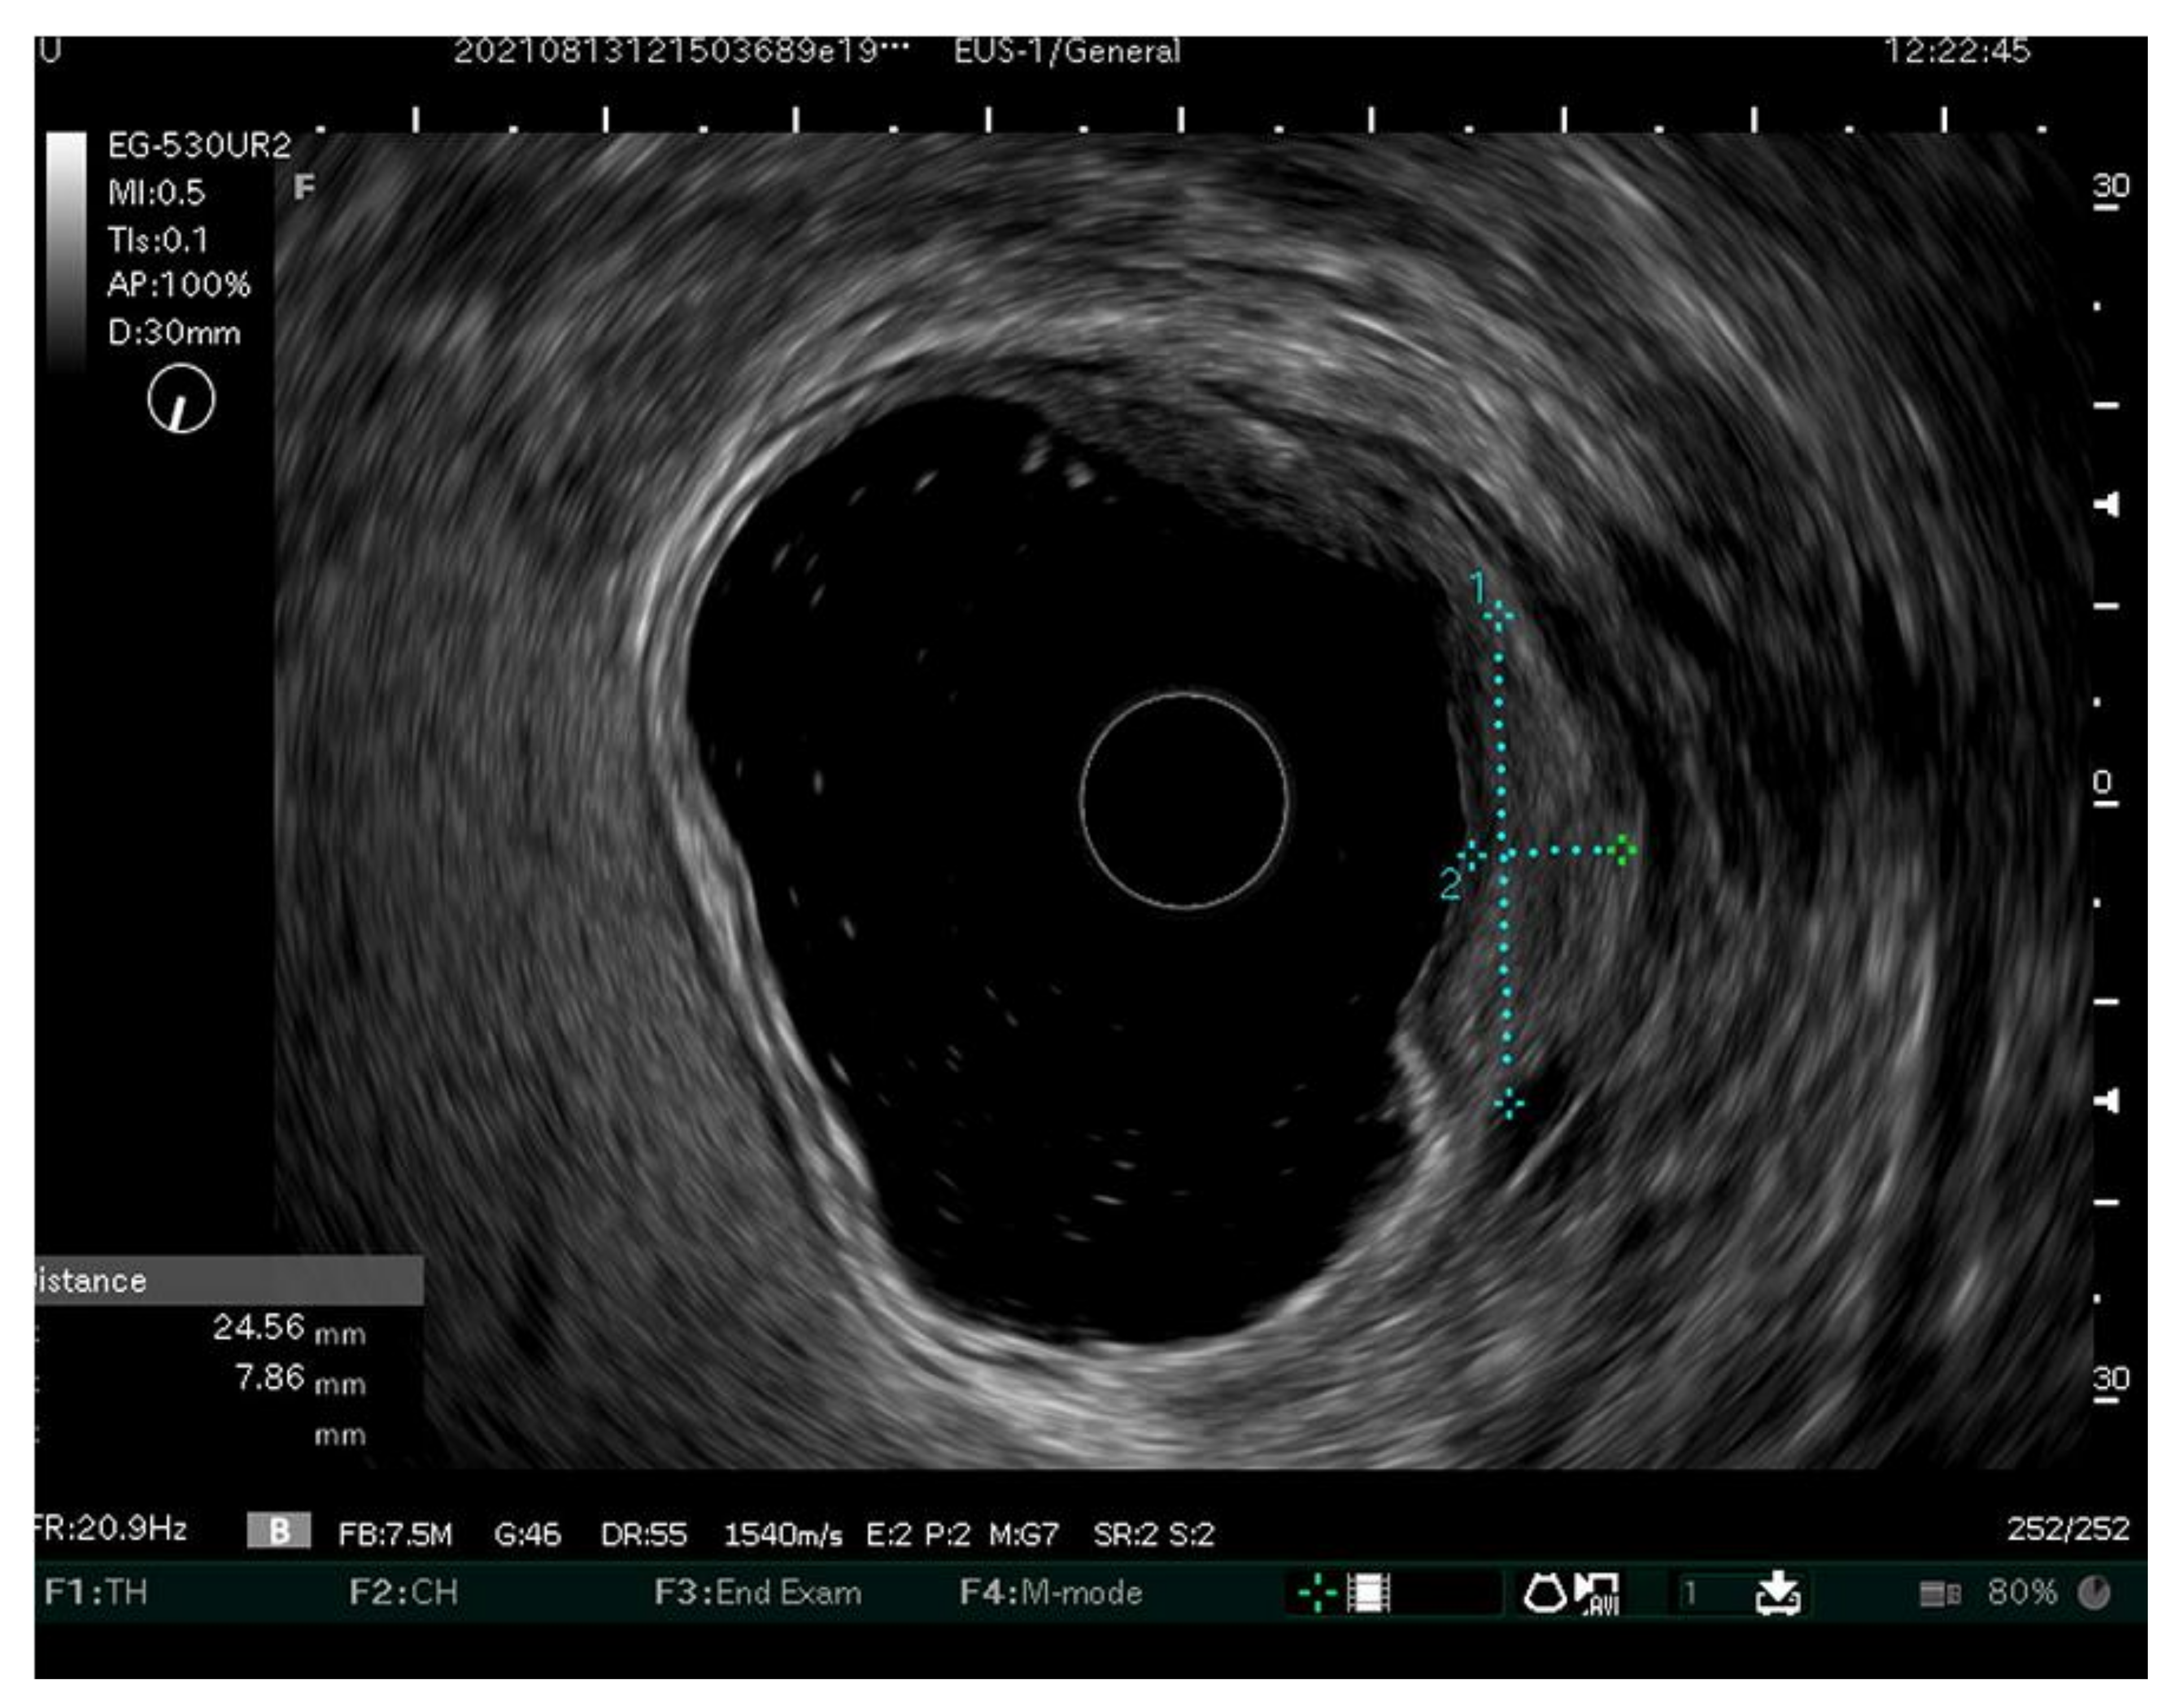

- Choi, J.; Kim, S.G.; Im, J.P.; Kim, J.S.; Jung, H.C.; Song, I.S. Endoscopic prediction of tumor invasion depth in early gastric cancer. Gastrointest. Endosc. 2011, 73, 917–927. [Google Scholar] [CrossRef]

- Tsujii, Y.Y.; Hayashi, Y.; Ishihara, R.; Yamaguchi, S.; Yamamoto, M.; Inoue, T.; Nagai, K.; Ogiyama, H.; Yamada, T.; Nakahara, M. Diagnostic value of endoscopic ultrasonography for the depth of gastric cancer suspected of submucosal invasion: A multicenter prospective study. Surg. Endosc. 2022. [Google Scholar] [CrossRef]